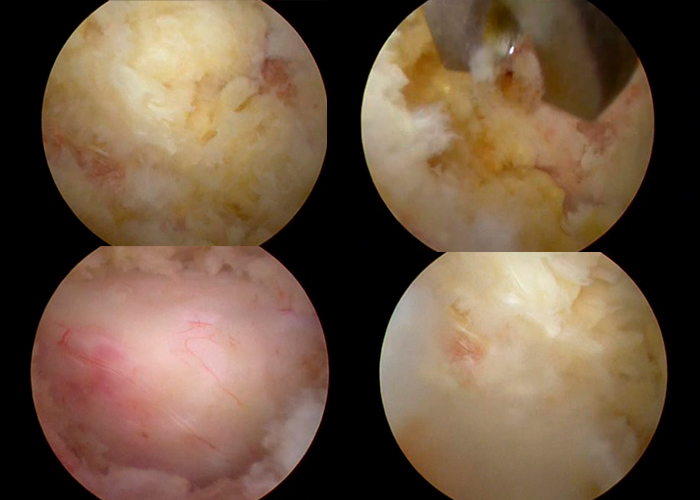

Operación

Se le coloca Membrana para proteger la dura madre Duragen.

Postoperatorio

El paciente actualmente deambula con normalidad, habiendo desaparecido completamente los dolores.

En piernas como la sensación de debilidad.

El caso fue un éxito con recuperación inmediata a las 8 horas.

La marcha del paciente normal a partir de las 6 horas de intervención sin muletas.

Dolor ausente.

Desaparecieron los calambres y la sensación de adormecimiento de las piernas.